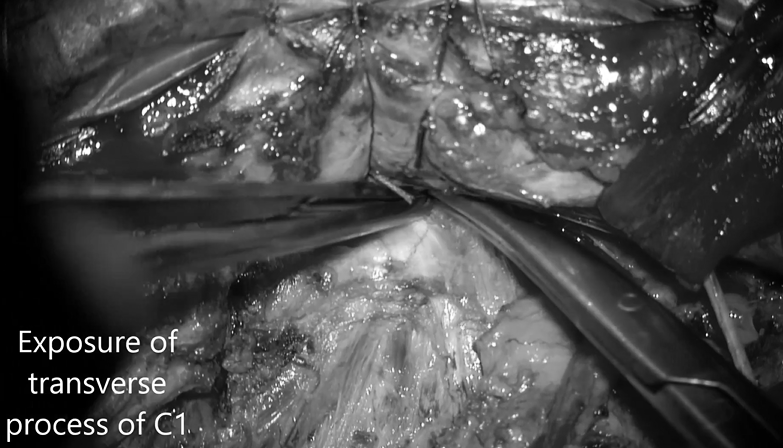

▼暴露C1寰椎横突

▼打开C1横突孔以暴露椎动脉

▼颅外椎动脉V3段骨膜下剥离术解剖动脉,保留静脉丛